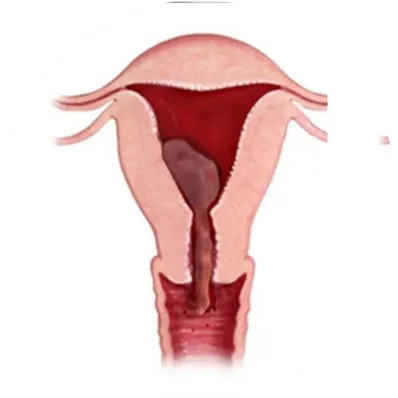

What is D&C / MTP?

D&C (Dilation and Curettage): A short surgical procedure where the cervix is gently dilated, and tissue is removed from the uterine lining. It is performed for abnormal uterine bleeding, incomplete miscarriage, or to diagnose endometrial conditions.

MTP (Medical Termination of Pregnancy): A legal and medically supervised termination of pregnancy using medicines or surgical methods, as per the MTP Act in India, within the prescribed gestational limits and conditions.

Both procedures are performed by qualified gynecologists to ensure safety, privacy, and care.